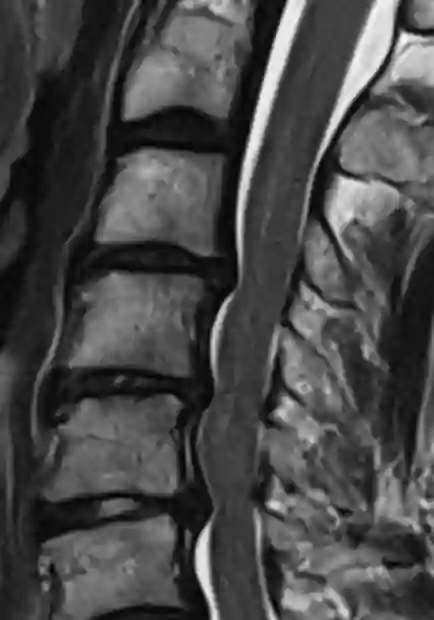

Absolute Spinalkanalstenose im MRI

Absolute Spinalkanalstenose im axialen T2 MRI Bild. Der Liquorsaum lässt sich auf diesem Bild im Spinalkanal nicht mehr abgrenzen.